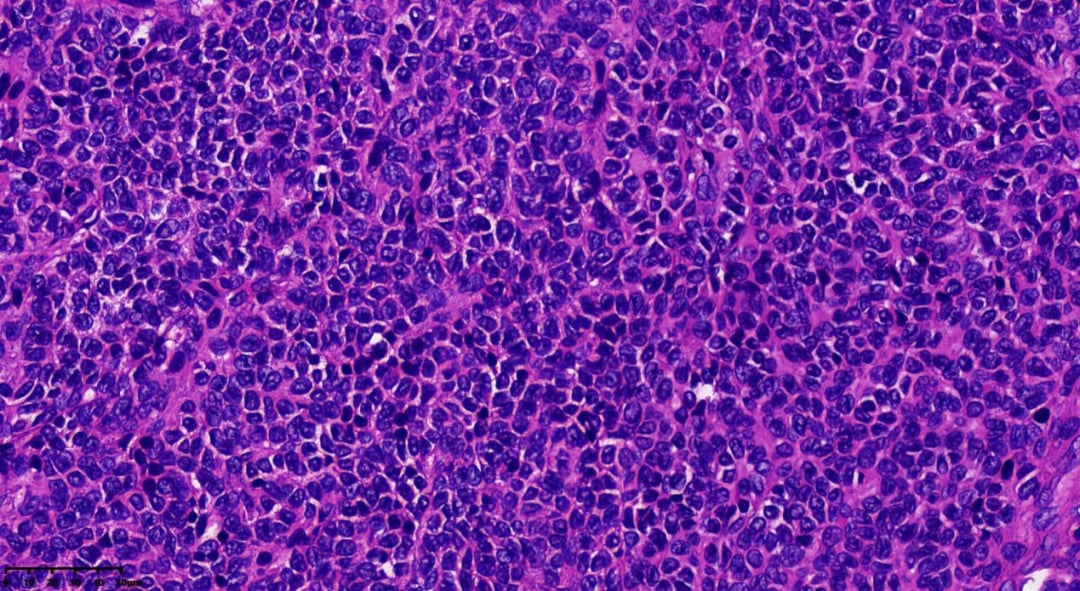

瘤细胞一般胞质稀少,大小较一致,细胞界线不清,卵圆形或多边形,细胞核轮廓不规则,可见核沟或核呈咖啡豆状。核分裂象少见

可见Call-Exner小体

- 组织病理学:瘤组织排列模式多样,同一肿瘤内可能出现多种结构,包括弥漫性、结节状、小梁状、条索样、岛屿状、滤泡状、波浪状、脑回样及肉瘤样。少数病例可见囊性变区域,甚至形成假乳头。瘤细胞通常胞质稀少、淡染,大小相对一致,界线不清,呈卵圆形或多边形,细胞核轮廓不规则,可见核沟或呈咖啡豆状。核分裂象通常较少见,75%的病例中每10个高倍视野(HPF)少于3个。

- Call-Exner小体是AGCT的典型特征,表现为瘤细胞围绕中心腔无定向排列,中心腔内含有核碎屑的嗜酸性分泌物或基底膜样粉染物。